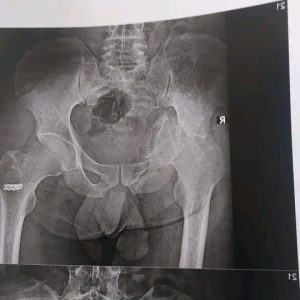

ومن جانبه قال الدكتور مجدي القاضي انه تم تقييم الحالة الصحية لأحد المرضي الأشقاء من أهالى غزة، ويبلغ من العمر 41 عاما ويعانى من خلع بمفصل الحوض منذ ٦ شهور، وعلى الفور تم إجراء العملية الجراحية للمريض وتركيب مفصل حوض كامل، مضيفاً أن ادارة المستشفي تولي اهتمام كبير ورعاية مستمرة لجميع مصابي غزة منذ ان وطأت اقدامهم داخل المستشفي الجامعي، وذلك تنفيذاً لتوجيهات الدكتور حسان النعماني رئيس الجامعة واهتمامه البالغ بمتابعته المستمرة لمستوي التحسن لحالتهم الصحية.

وقال الدكتور عبدالرحمن الشيخ انه تم استقبال المريض بقسم العظام وعمل الفحوصات والتحاليل المخبرية والاشاعات اللازمة وعلي الفور تم تشكيل الفريق الطبي المعالج الذي اجري العملية الجراحية ببراعة كبيرة، حيث بلغت تكلفة المفصل ٨٥ الف جنيه كتبرع من قسم العظام، موضحاً ان الفريق الطبي تكون من الدكتور ياسر عثمان استاذ جراحة العظام، الدكتور حسام حسنى والدكتور محمد شحاتة والدكتور عبدالرحمن بهاء مدرسين مساعدين بقسم العظام، الدكتور اسلام النحاس والدكتور مصطفى عبداللاه والدكتور يوسف راضى معيدين بقسم العظام، والدكتور على الشيخ والدكتور محمد جمال نواب سنيور بقسم العظام، بينما ضم فريق التخدير بقيادة الدكتور فوزي عباس كلاً من، الدكتور احمد عزمى مدرس مساعد تخدير، والدكتور عمرو عبد الصبور و الدكتورة ريهام رجب نواب سنيور بالقسم، وشكر خاص لفريق الهيئة التمريضية علي مابذلوه لإنجاز هذا العمل الانساني الكبير.